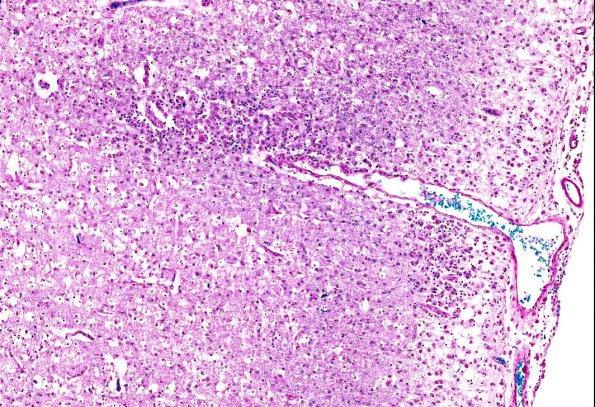

Washington University Experience | MISCELLANEOUS | Familial erythrophagic lymphohistiocytosis | 2B6 Familial erythrophagic lymphohistiocytosis (AANP 1980, Case 2) LFB-PAS 6.6X

2B6,7 Higher magnification image of cortical gray matter pathology shows numerous perivascular and parenchymal histiocytes (LFB-PAS)